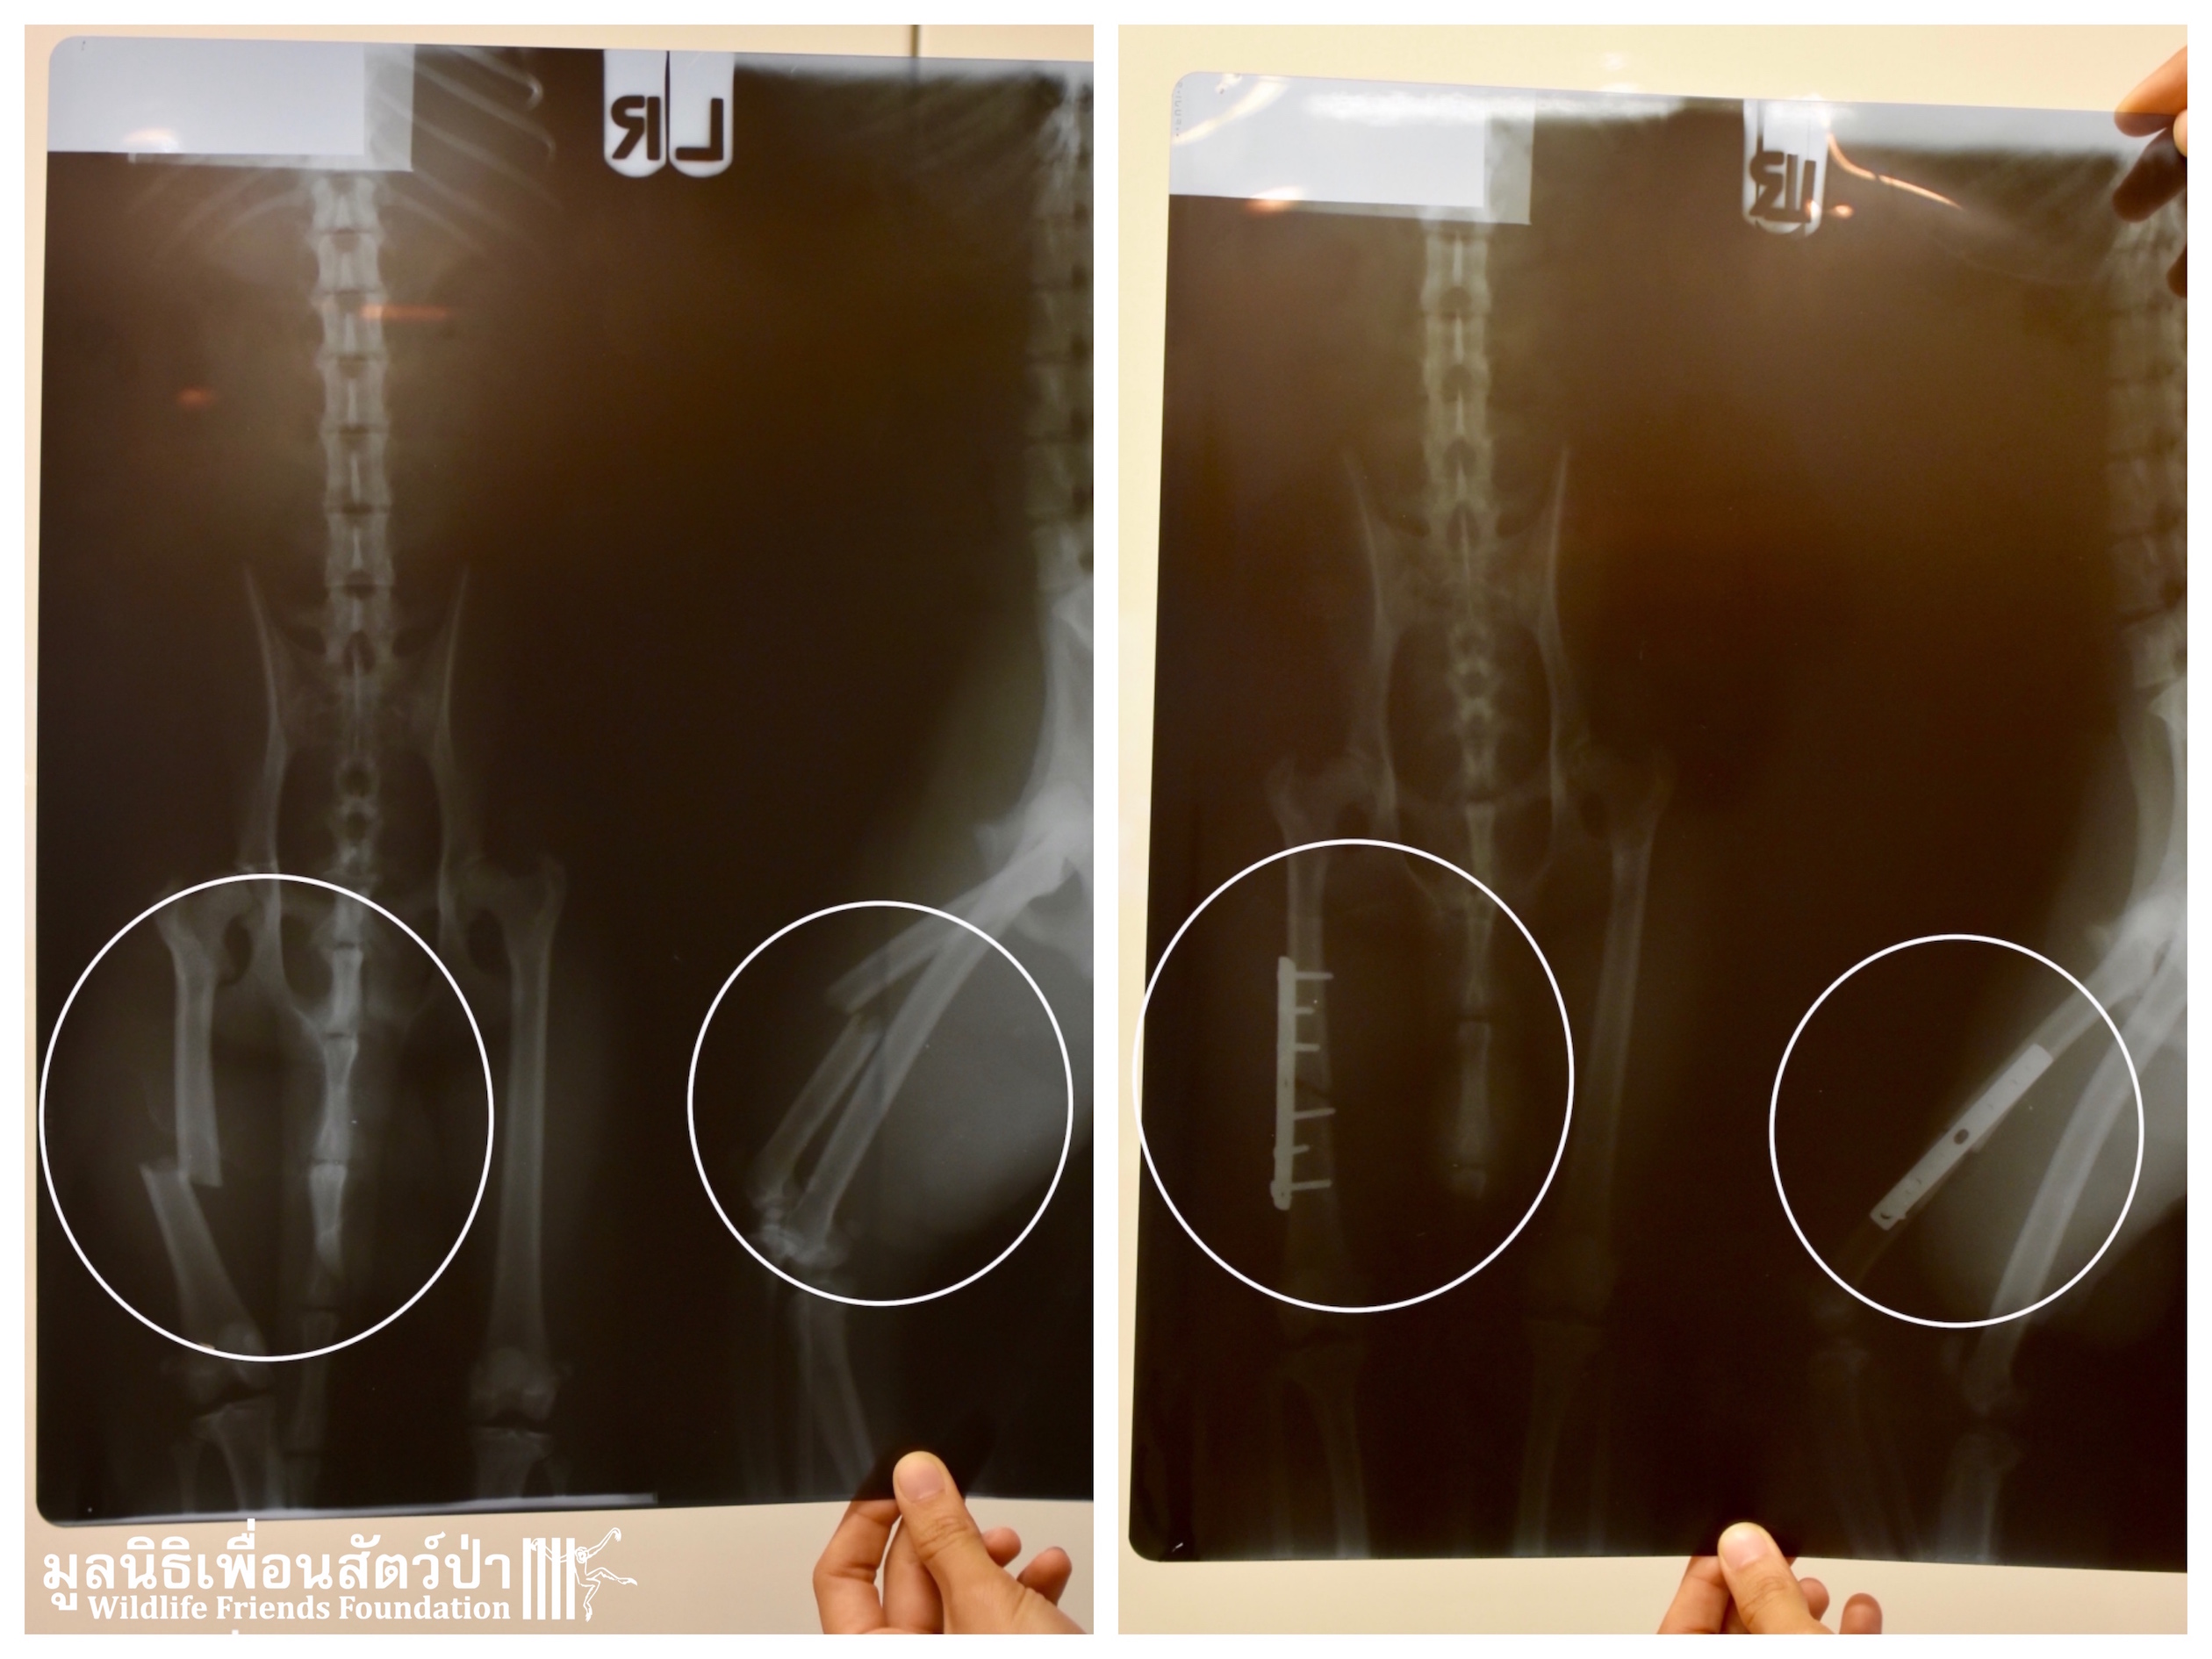

Five days ago a seriously injured adult male long-tailed macaque (Macaca fascicularis) arrived at the WFFT Wildlife Rescue Hospital for urgent treatment. He was brought to WFFT by a local police division after being hit by a speeding vehicle during a road clearance for an official visit in the area, many cars were moved from the road, and in the confusion the macaque was hit. He sustained a multitude of injuries all over his body including a severely fractured leg. Upon arrival he was very weak and his breathing was labored indicating that he had sustained serious internal injuries. The WFFT Vet Team straight away started emergency surgery, after a long 2-hour surgery all his wounds were cleaned and stitched up. The prognosis was not looing good for this big boy, but to our amazement the following morning we found him sat up straight in and very alert in his treatment enclosure. The next day he was taken to a local animal hospital were a bone specialist perform surgery to fix his broken leg, a metal plate was inserted to help rejoin the broken bone.